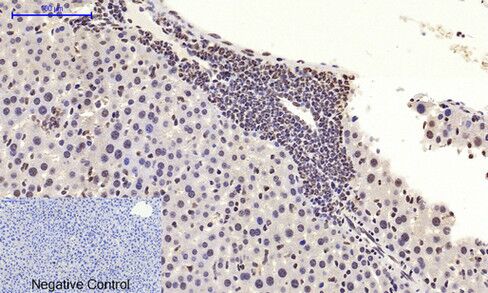

Immunohistochemical analysis of paraffin-embedded Human lung carcinoma tissue using c-Myc Polyclonal Antibody.